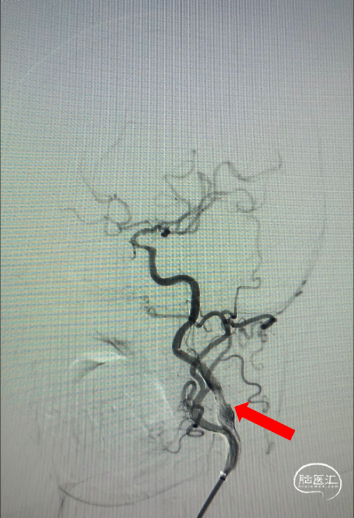

➤术后造影

从影像可见球囊扩张后支架内再狭窄情况明显改善。